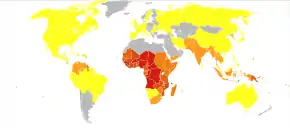

The WHO estimates that in 2021 there were 247 million new cases of malaria resulting in 619,000 deaths.[5] Children under 5 years old are the most affected, accounting for 67% of malaria deaths worldwide in 2019.[192] About 125 million pregnant women are at risk of infection each year; in Sub-Saharan Africa, maternal malaria is associated with up to 200,000 estimated infant deaths yearly.[30] Since 2015, the WHO European Region has been free of malaria. The last country to report an indigenous malaria case was Tajikistan in 2014.[5] There are about 1300–1500 malaria cases per year in the United States.[26] The United States eradicated malaria as a major public health concern in 1951,[193] though small outbreaks persist.[194] Locally acquired mosquito-borne malaria occurred in the United States in 2003, when eight cases of locally acquired P. vivax malaria were identified in Florida, and again in May 2023, in four cases, as well as one case in Texas,[195] and in August in one case in Maryland.[196] About 900 people died from the disease in Europe between 1993 and 2003.[70] Both the global incidence of disease and resulting mortality have declined in recent years. According to the WHO and UNICEF, deaths attributable to malaria in 2015 were reduced by 60%[79] from a 2000 estimate of 985,000, largely due to the widespread use of insecticide-treated nets and artemisinin-based combination therapies.[76] Between 2000 and 2019, malaria mortality rates among all ages halved from about 30 to 13 per 100,000 population at risk. During this period, malaria deaths among children under 5 also declined by nearly half (47%) from 781,000 in 2000 to 416,000 in 2019.[77]

Malaria is presently endemic in a broad band around the equator, in areas of the Americas, many parts of Asia, and much of Africa; in Sub-Saharan Africa, 85–90% of malaria fatalities occur.[197] An estimate for 2009 reported that countries with the highest death rate per 100,000 of population were Ivory Coast (86.15), Angola (56.93) and Burkina Faso (50.66).[198] A 2010 estimate indicated the deadliest countries per population were Burkina Faso, Mozambique and Mali.[199] The Malaria Atlas Project aims to map global levels of malaria, providing a way to determine the global spatial limits of the disease and to assess disease burden.[200][201] This effort led to the publication of a map of P. falciparum endemicity in 2010 and an update in 2019.[202][203][204] As of 2021, 84 countries have endemic malaria.[5]

The geographic distribution of malaria within large regions is complex, and malaria-afflicted and malaria-free areas are often found close to each other.[205] Malaria is prevalent in tropical and subtropical regions because of rainfall, consistent high temperatures and high humidity, along with stagnant waters where mosquito larvae readily mature, providing them with the environment they need for continuous breeding.[206] In drier areas, outbreaks of malaria have been predicted with reasonable accuracy by mapping rainfall.[207] Malaria is more common in rural areas than in cities. For example, several cities in the Greater Mekong Subregion of Southeast Asia are essentially malaria-free, but the disease is prevalent in many rural regions, including along international borders and forest fringes.[208] In contrast, malaria in Africa is present in both rural and urban areas, though the risk is lower in the larger cities.[209]